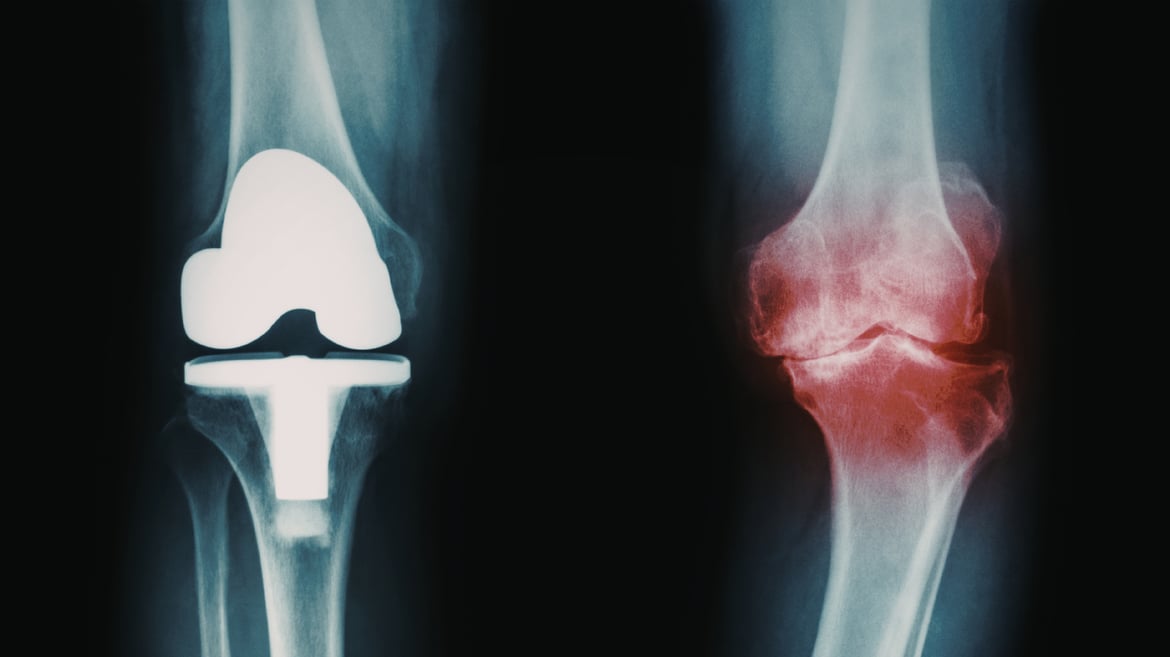

Knee replacement surgery -ray comparison of healthy and arthritic knee

Stem Cell Therapy for Knee Osteoarthritis: An Alternative to Knee Replacement

The knee joint is relatively straightforward to access via injection, making it suitable for regenerative treatment. In contrast, knee replacement surgery is often more complex and does not always deliver the same consistent outcomes as hip replacement. For patients seeking alternatives to joint replacement, stem cell therapy for knee osteoarthritis is becoming an increasingly discussed option.

Given the growing body of evidence supporting their effectiveness, combined with their relative ease of administration via joint injection, mesenchymal stem cells represent a viable treatment option for selected patients with knee osteoarthritis.

For individuals seeking to delay or avoid knee replacement surgery, stem cell therapy may offer a regenerative approach focused on cartilage repair, inflammation reduction and functional improvement.